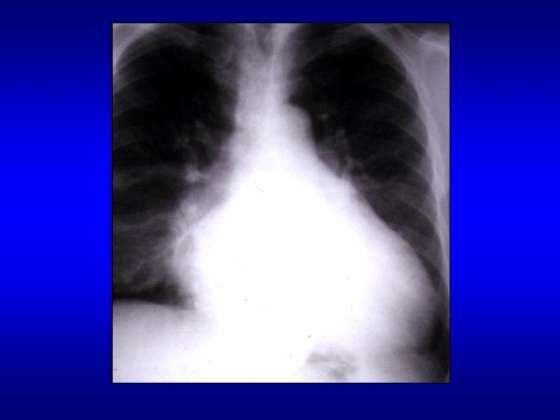

APARATUL RESPIRATOR

APARATUL RESPIRATOR Omul traieste intr-o sfera de aer, indispensabila vietii. Aparatul respirator mijloceste contactul omului cu aerul si este alcatuit din doi plamani si din condCiteste tot ... 553 cuvinte